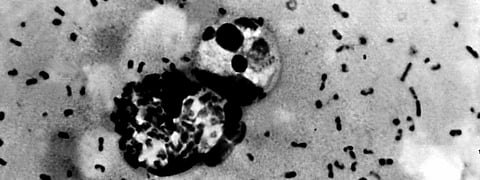

Plague manifests in three known forms: Bubonic, septicemic and pneumonic. Bubonic plague turns to pneumonic plague if not treated. According to the country nodal Institut National de Recherche Biomédicale laboratory in Kinshasa, of the 45 cases reported, two were of septicemic plague and the rest were of bubonic plague. But the WHO bulletin said all the three types of plague are present in the country now.

Actually and fortunately, cases of resistance of Yersinia pestis, the pathogen that causes plague were very rare and few had been reported in the scientific literature, Bertherata said.